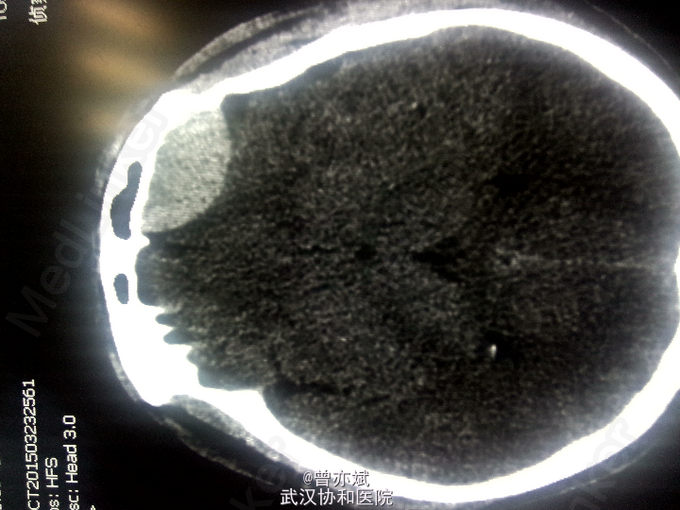

因“车祸伤1日余”入院。 现病史:患者1日前因车祸伤及头部,伤后神志昏迷,呼之不应,急送至当地医院,行CT检查示左额硬膜外血肿,并行清创缝合术,今为求进一步治疗来我院就诊,急诊以“脑外伤”收入我科。 病程中,患者神志昏迷,查体不合作。

查体:T 36.9℃,P 70次/分,R 20次/分,BP 128/82mmHg,查体不合作,神志浅昏迷,营养发育良好,皮肤及淋巴结未及明显异常,头颅大小正常,无畸形,头发分布正常,左额部软组织损伤,心肺腹未及明显异常。双下肢无水肿,生理反射存在,病理反射未引出。 专科查体:神志浅昏迷,GCS评分3+3+4分,左侧瞳孔直径6mm,对光反射消失,右侧瞳孔直径4mm,对光反射存在,四肢肌力2级,生理反射存在,病例反射未引出。 辅助检查:外院及我院急诊CT示左侧额部硬膜外血肿。急诊CT:1、左侧额部硬膜外血肿,厚度为23mm;2、少量蛛网膜下腔出血;左侧额骨线性骨折累及左侧眶顶、内侧壁及眶突,左侧眼眶内侧壁局部凹陷,考虑为外上性改变,左侧筛窦积液、积血、蝶窦积液。